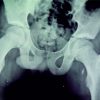

A 22-year-old male patient presented in our outpatient department with pain in the right sternoclavicular region which aggravated on overhead activities. He sustained a fall on the right outstretched hand during a bike accident 8 h before presenting to us. On clinical examination, there was tenderness over the medial sternoclavicular joint as well as posterior dip in the medial clavicle (Fig. 1). This led us to clinically suspect a posterior sternoclavicular dislocation. The radiographs appeared normal (Fig. 2) so we advised a 3D reconstruction CT imaging of the right clavicle and sternum. CT images were suggestive of a posterior dislocation of the medial end of the clavicle (Fig. 3). However, one section of the CT appeared to show a flake of bone attached to the sternum. Medial clavicular physeal injury was a secondary diagnosis which was kept in consideration. We decided to take the patient up for closed reduction under anesthesia and covert to open reduction if closed attempts failed.